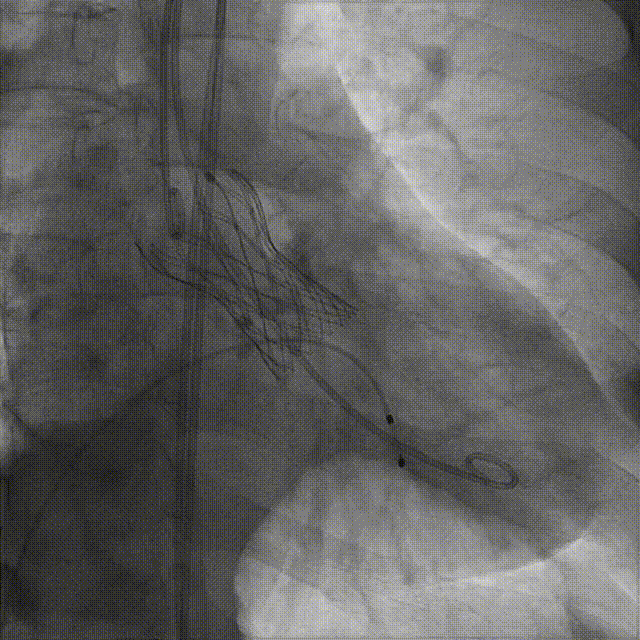

外周分析

外周概览(钙化)

外周概览

入路血管走形良好,无明显附壁钙化,弓部条件良好,预估过弓、跨瓣顺利。